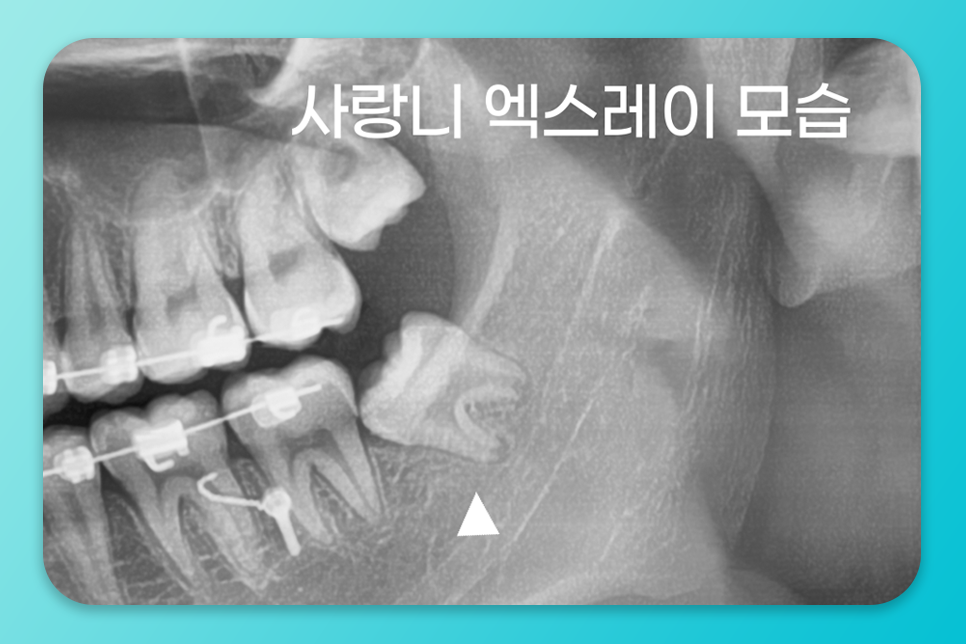

이런 패턴이 반복된다면

X-ray 검사로 매복 정도와

맹출 방향, 공간 여부를 확인하고

필요 시 발치 시기를 잡는 게 좋습니다.

특히 매복 사랑니를

오래 두면 드물지만

물혹이 생길 수 있고

커지면 주변 치아 뿌리나

잇몸뼈를 녹이는

문제로 이어질 수 있어요.

이런 경우에는 너.무 늦지 않게

발치를 권장드립니다.